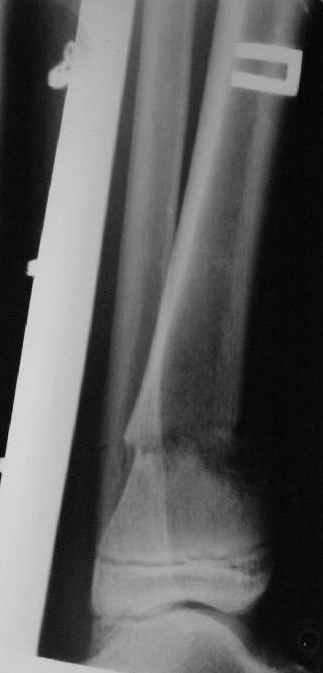

Это сросшийся перелом малоберцовой кости. И ложный сустав

н\3 б\берцовой кости.

в гипсе

Промежуточный